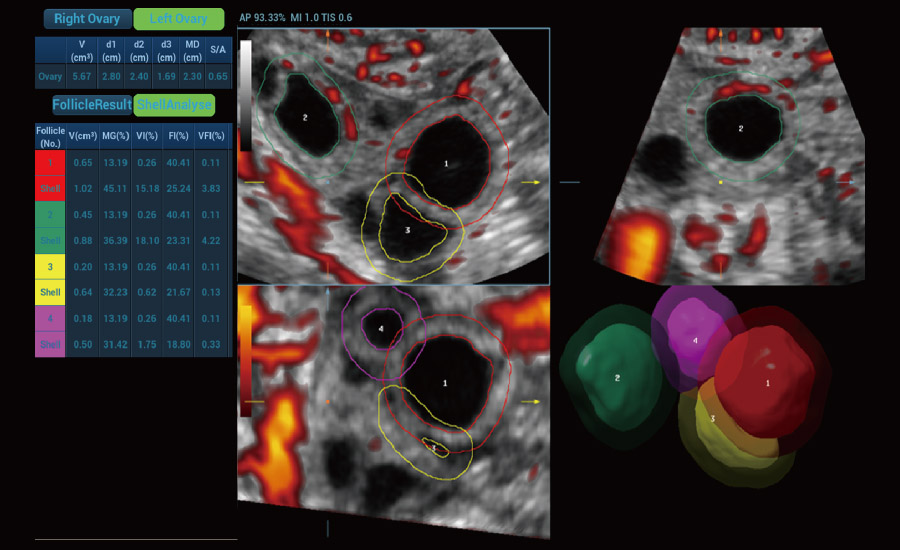

UMA 3D ā Fluxo sanguĆneo perifolicular

A tecnologia inovadora elimina as limita??es das tradicionais imagens com Doppler. Com resolu??o espacial e sensibilidade de fluxo ultra-altas, permite a detec??o de perfus?es de fluxos muito sutis e lentos, ampliando assim a aplica??o clĆnica da avalia??o qualitativa e quantitativa do ultrassom no cĆ©rebro fetal, rins, placentas, endomĆ©trios, ovĆ”rios etc.

UMA (angiografia ultramicroscĆ³pica)

Fertilidade

Por meio da combina??o de algoritmos avan?ados e do conhecimento especĆfico da regi?o, a inovadora solu??o Smart Scene permite a identifica??o automĆ”tica das caracterĆsticas do tecido e fornece diagnĆ³stico especĆfico dos Ć³rg?os com informa??es completas. Com base na identifica??o automĆ”tica de cenĆ”rios, a solu??o realiza n?o apenas a varredura 2D inteligente com configura??es e medidas automĆ”ticas, mas tambĆ©m oferece informa??es 3D abrangentes em todas as etapas, desde a otimiza??o de imagens volumĆ©tricas atĆ© a difĆcil obten??o de planos 2D, e a quantifica??o durante todo o procedimento. Ele ajuda a reduzir em grande parte a dependĆŖncia de habilidades clĆnicas, ao mesmo tempo que aumenta a precis?o, a confian?a e a eficiĆŖncia no diagnĆ³stico.